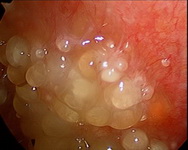

萬芳醫院從2000年開始嘗試第一例的腫瘤減量手術合併腹腔熱化療,治療胃癌合併有腹腔轉移的病例,並於2002年開始常規的施行此項治療, 隨後並擴展到其他各式各樣的癌症。

Wan-Fang Hospital started to perform CRS (cytoreduction surgery) plus HIPEC (hyperthermic intraperitoneal chemotherapy) at 2000, to treat the first case of gastric cancer with peritoneal metastasis. Since 2002, it became a regular procedure and treat many kinds of cancers at the present.